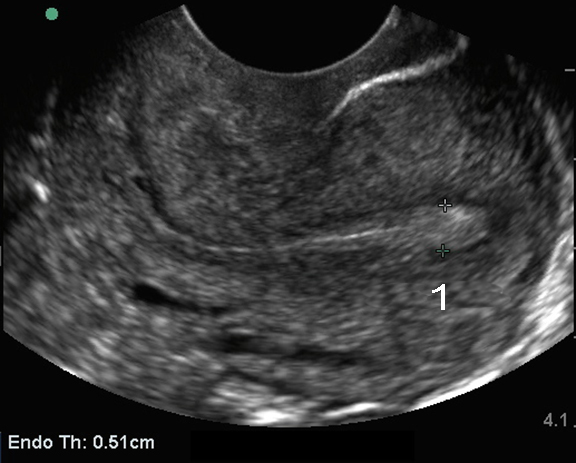

骨盤の経膣子宮: 子宮内膜測定画像

後傾子宮

子宮内膜